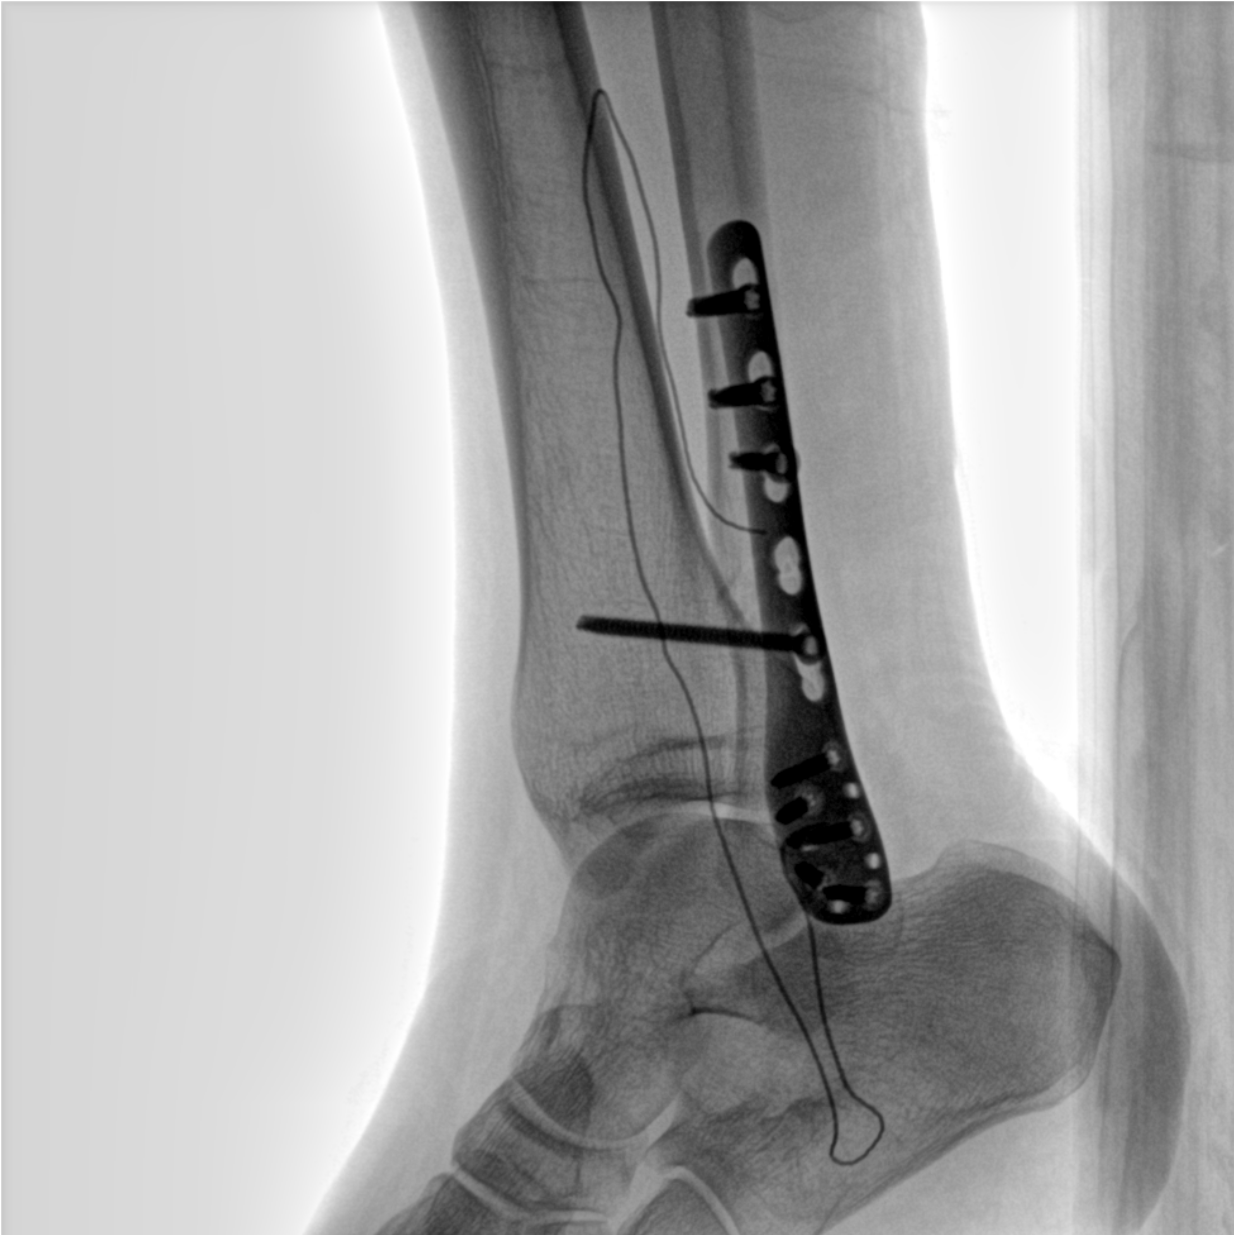

術中三維成像和橫斷面圖像提供多角度的手術診斷信息,輔助醫生進行術中評估判斷,諸如骨折復位情況和內植入螺釘的尺寸和位置,輔助手術更好地完成。

平板垂直升降運動 便于術中微調平板與拍攝主體的距離,更加貼近病灶體,成像范圍更大,圖像更清晰。